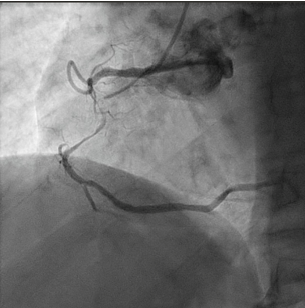

A 73-year-old man was hospitalized due to acute coronary syndrome. Right coronary artery angiography revealed a severely tortuous vessel with long critical stenosis (Figure 1).

Coronary angioplasty was performed by first advancing a Sion guidewire (Asahi), followed by a Launcher Amplatz right 6F guide catheter (Medtronic) with a 2.5 x 15-mm semicompliant balloon. Next, a 3 x 48-mm everolimus-eluting stent was advanced with a GuideLiner 6F extension catheter (Teleflex). After inflation, the stent failed to expand as a result of perforation of the drug-eluting balloon (Figure 2); only partial opening of the ends of the stent was observed, with consequent entrapment of the stent and balloon. Traction proved unsuccessful for retrieval of the device and the balloon hypotube shaft was torn; consequently, the device was lost in the right coronary artery.